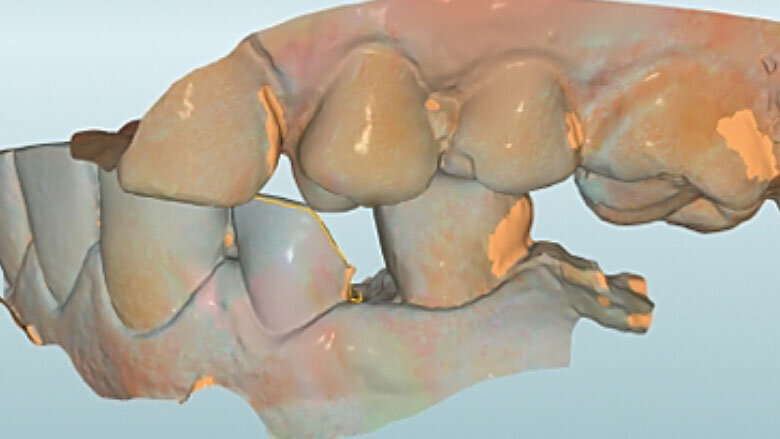

Fig. 5. Tras el escaneo intraoral se estableció el límite de la preparación.

Fig. 6. Mediante un escaneo vestibular se trasladó la intercuspidación habitual.

Preparación y escaneo intraoral

Antes de la preparación se determinó el color dental 2M2 mediante la VITA Toothguide 3D-MASTER (VITA Zahnfabrik) y se seleccionó la pieza en bruto correspondiente. Se colocó adhesivamente una espiga de fibra de vidrio para incrementar la retención de la posterior reconstrucción de composite. Durante la preparación, únicamente se acortaron las paredes y se incorporó un chamfer en la zona del defecto. Se redondearon sistemáticamente los bordes afilados en la cavidad. Antes del escaneo intraoral fue posible tratar con composite de forma mínimamente invasiva la caries proximal en el diente 34 gracias al buen acceso por mesial.